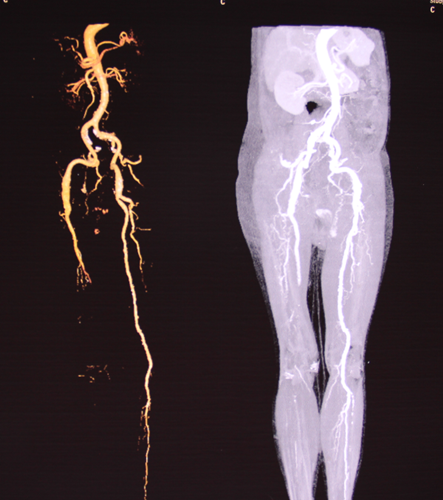

患者于夜晚20:10由当地医院救护车转送入我院。当时患者右下肢缺血严重,双侧股动脉巨大搏动性包块,肢体保全几率极低!值班医生丁语接诊病人后,意识到患者病情危重,立刻请彩超室值班医生王敏进行床旁迅速定性诊断,发现患者右下肢动脉全程血栓形成,双侧股动脉巨大动脉瘤合并血栓形成。我院血管外科专家王兵副院长得到汇报后指示立即为患者进行下肢动脉CTA检查,进一步明确诊断。CT室值班医生姜喜峰迅速给以 “绿色通道”,使患者在入院不到1小时就拿到了影像学结果。王兵副院长和血管外科崔文军副主任根据患者CTA结果,确诊该患者是一例罕见双侧股动脉巨大动脉瘤并附壁血栓并右下肢急性动脉栓塞。

术前CTA提示双侧巨大型股动脉瘤、右髂动脉瘤

断层提示:右髂总动脉瘤